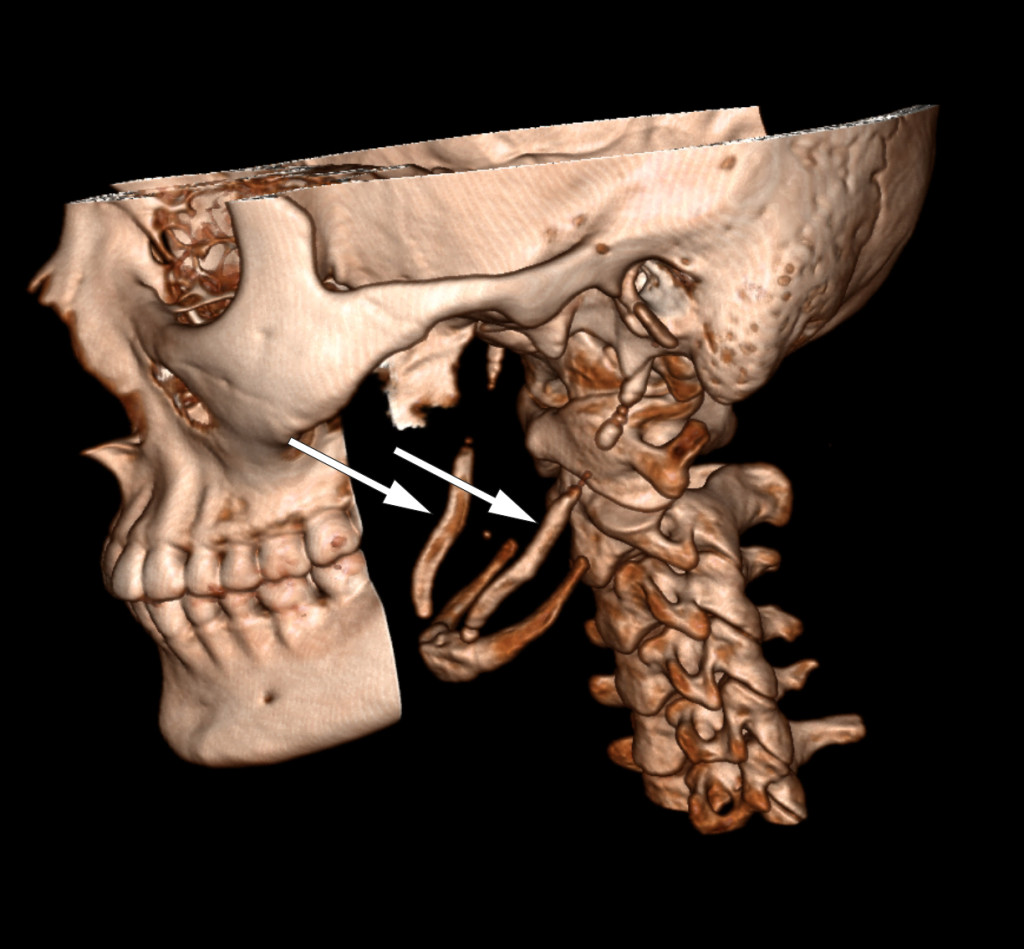

Symptomene ble fremprovosert og forverret med sidebøy og rotasjon av hodet mot høyre. Anamnestisk hadde hun hatt en lignende og forbigående episode to år tidligere. Det var ikke noe hode- eller nakketraume i sykehistorien. Klinisk undersøkelse var upåfallende, foruten palpasjonsømhet peritonsillært og over venstre nakkehalvdel. Omfattende utredning med nevrofysiologiske, bildediagnostiske og øre-nese-hals-undersøkelser viste normale funn. CT-undersøkelse av nakken avdekket forkalkning i ligamentum stylohyoideum bilateralt (se piler), noe som kunne forklare pasientens symptomer.